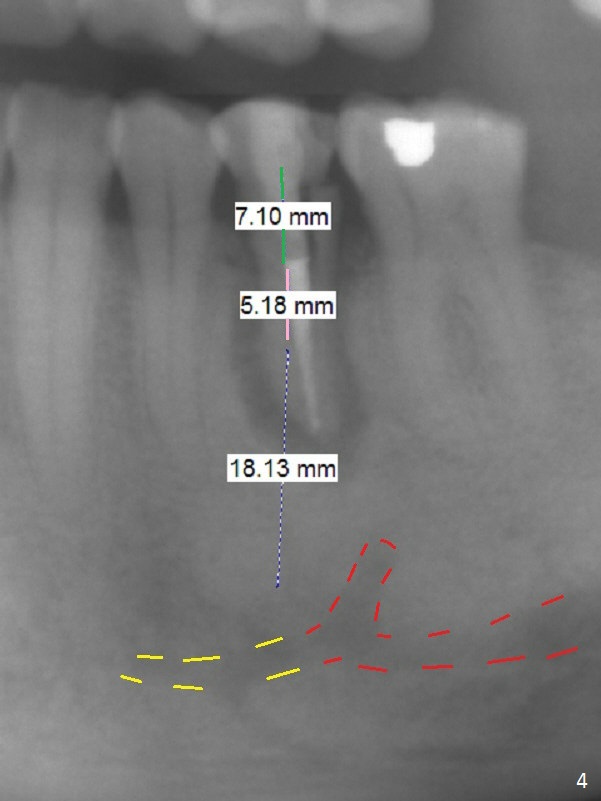

A 53-year-old man (probably bruxer, long roots) has 3 missing teeth (Fig.1 #14,18,29) and 1 fractured tooth (Fig.2 #20). The fractue is associated with deep buccal pockets. The buccal plate is most likely defective. After extraction (Metronidazole), start osteotomy lingual and mesial (Fig.3 red long arrow) to reduce damage to the Mental Loop (Fig.4 red dashed line). Damage to the Incisive Canal (yellow dashed line, the continuum of the Inferior Alveolar Canal after giving off the Mental Loop) is less significant. Since the defect is long, use the longest implant and place it deep. A long abutment (7 mm, green) with 5 mm cuff (pink) is required. To have sufficient buccal gap for bone graft and probably membrane, the smallest two-piece implant is necessary (3.8 mm).